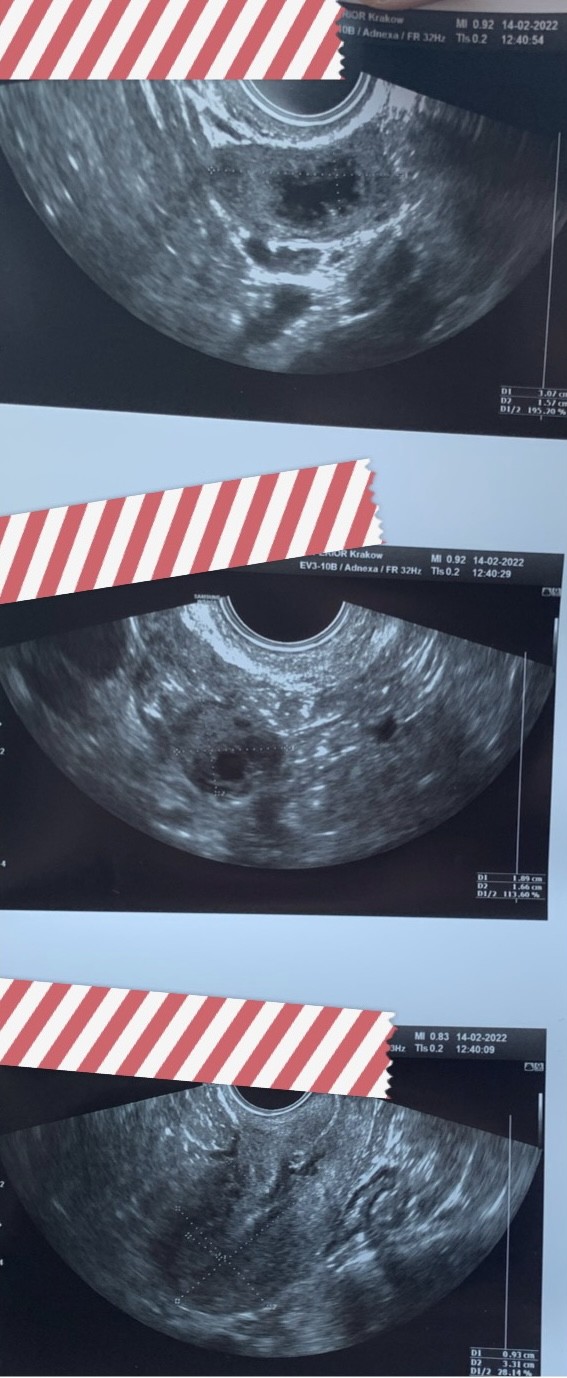

Ja dziś chciałam sobie zmierzyć pęcherzyk… Endo 9mm

Jajnik lewy z widocznym ciałkiem żółtym zatoka Douglasa bez wolnego płynu.

Miałam mieć owu dopiero jutro lub po jutrze wg flo, a tu już po ptokch (13dc).

To co złapałam na testach owu to już był ten pik?

A tu starania dopiero co rozpoczęte w tym cyklu 🤯😤😳😢🤬